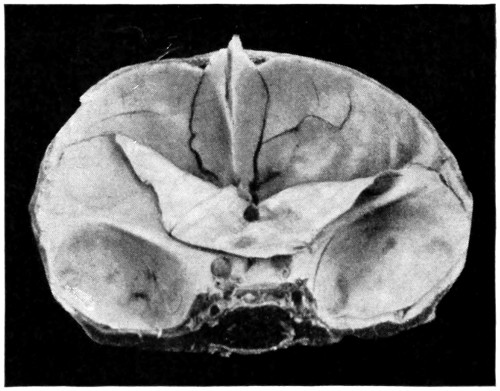

Fig. 20. An Occipital Cephalocele. (For further description, see text.)

1. Occipital cephaloceles—the commonest variety—occupy, anatomically, two positions (1) between the two lower segments of the occipital bone (inferior occipital cephaloceles), often involving the foramen magnum and sometimes complicated by a condition of cervical spina bifida, and (2) between the two upper segments of the occipital bone (superior occipital cephaloceles), occasionally involving the posterior fontanelle.

The tumour may possess a broad base or may be definitely pedunculated. In the former instance the gap in the bone may be of considerable size and the margins everted: in the latter case, the hole may be quite small.

The deformity is frequently associated with other congenital defects—hydrocephalus, microcephalus, spina bifida, hare lip, hernia, and talipes.

Sincipital cephaloceles are usually quite small, but the occipital variety and those situated in[35] the region of the anterior fontanelle frequently attain a great size (see Figs. 20-22).

Fig. 22. An Occipital Cephalocele. (For further description, see text.)

The following case serves to illustrate some of these facts:[9]—

The child was 3 months old, and presented a tumour, the size of an orange, situated between the occipital protuberance and the nape of the neck. The mass was pedunculated, the stalk being about the size of a four-shilling piece in diameter. It was soft, translucent, irreducible, and swelled up on coughing. An attempt at removal was carried out, and, after incising the outermost layers, three ounces of cerebro-spinal fluid escaped. A second tumour was then found occupying the base of the swelling. This was also punctured, more fluid escaping. Both sacs were cut away and the wound sewn up. Death occurred on the third day, preceded by convulsions, retraction of the head and neck, and high fever. The autopsy showed that the fontanelles were widely open, the anterior measuring 4 inches from side to side and 21⁄2 from before backwards. The bones of the vault were markedly thinned. In the subdural space there was a quantity of fluid, and the cerebral substance was soft and diffluent, the convolutions flattened, and the ventricles distended. There was a broad gap in the occipital bone, extending downwards into the foramen magnum, and in this situation the cerebellum had bulged backwards into the protruding mass. (See Fig. 22).